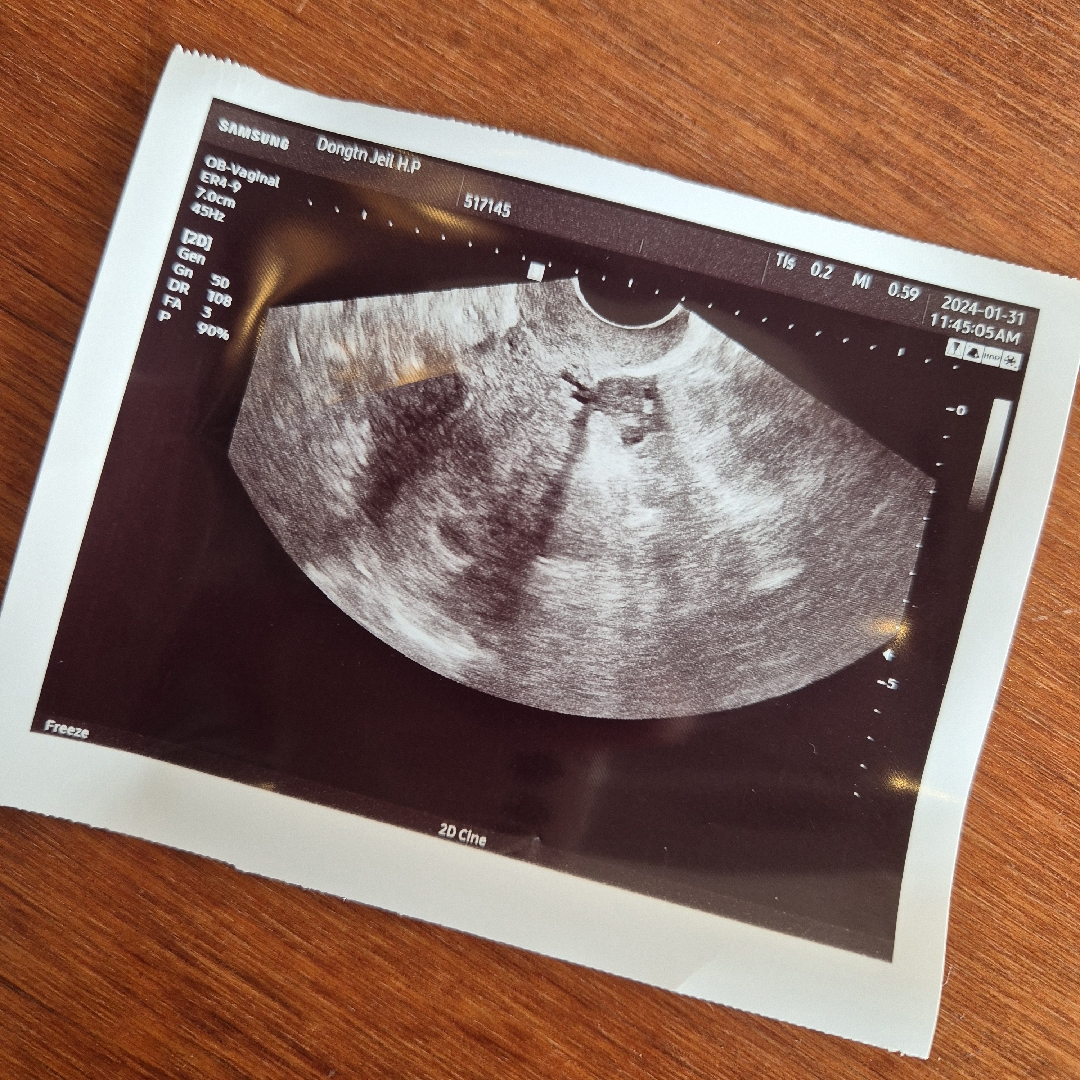

시험관 이식19일차 5주2일차 난황까지 볼 수 있나 기대했는데 아기집만 확인하고왔어요~ 쌤은 위치도,크기도 좋다고 다음주에 오면 아기집도 더 커지고 난황도 보일거라고 하시면서 초음파가 흐리게나왔다고 하셨는데 진짜 다른분들에 비해 많이 흐리네요ㅠ 병원 초음파마다 선명도가 다른걸까요..? 문제없겠죠..?